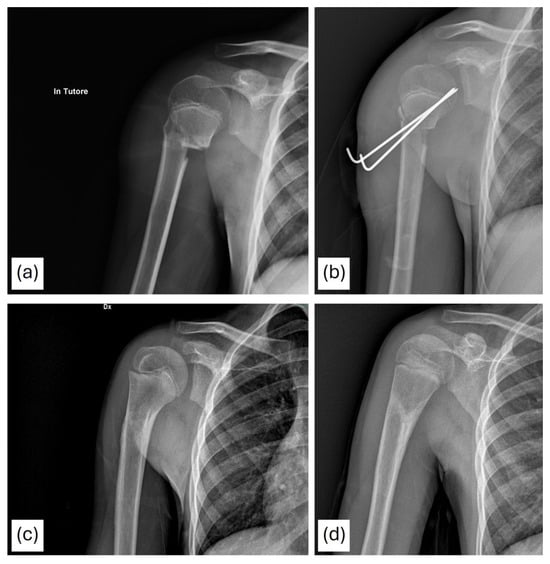

Non-Operative vs. Operative Treatment of Pediatric Proximal Humerus Fractures: Surgery Offers No Clinical or Economic Benefit, a Retrospective Study of 152 Children

by Tosca Cerasoli, Marina Magnani, Marco Todisco, Marianna Viotto, Grazia Chiara Menozzi, Giulia Alessandri, Cosma Caterina Guerra, Tiziana Pianta, Giulio Maria Marcheggiani Muccioli, Gino Rocca and Giovanni Trisolino

Children 2026, 13(1), 67; https://doi.org/10.3390/children13010067 - 31 Dec 2025

Background: Pediatric proximal humerus fractures (PHFs) typically heal well due to their strong remodeling potential, supporting non-operative management even in displaced injuries. However, surgery for Neer–Horowitz grade III–IV fractures has become more frequent despite limited evidence of superior outcomes. Methods: A retrospective analysis [...] Read more.

Background: Pediatric proximal humerus fractures (PHFs) typically heal well due to their strong remodeling potential, supporting non-operative management even in displaced injuries. However, surgery for Neer–Horowitz grade III–IV fractures has become more frequent despite limited evidence of superior outcomes. Methods: A retrospective analysis of 152 children (<14 years) treated for isolated PHFs at a tertiary pediatric orthopedic center (2004–2023) was performed. Clinical records and telephone follow-up provided demographic data, fracture classification, management, complications, and functional outcomes (QuickDASH, Tegner, return to sport). A direct cost analysis compared conservative and surgical pathways. Results: Of 152 patients, 133 were treated non-operatively and 19 surgically. Conservative management achieved excellent results across all fracture types: nearly all patients reported normal QuickDASH scores and full shoulder function. Among Neer III–IV fractures (n = 37), functional outcomes, activity levels, and sport resumption were similar between treatment strategies. Minor transient issues (pin migration, temporary stiffness, delayed return to sport) occurred only after surgery. No meaningful complications were observed in the conservative cohort. Mean costs differed substantially: €1452.09 for non-operative management versus €7832.12 for surgical treatment. Conclusions: Long-term outcomes of pediatric PHFs were uniformly excellent, regardless of fracture severity or treatment modality. Surgery did not improve recovery, function, or return to sport and was associated with higher costs and minor postoperative issues. Conservative management should remain the standard of care for nearly all pediatric PHFs, with surgery reserved for exceptional circumstances such as open fractures, neurovascular compromise, or failed closed reduction. Full article